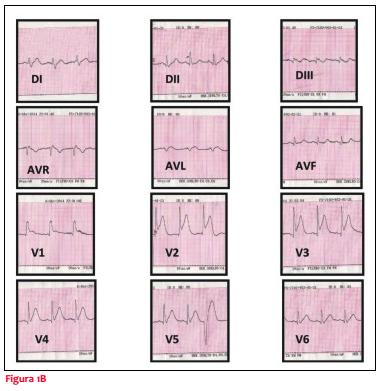

Recibe tratamiento antihistamínico intravenoso, una serie de salbutamol inhalatorio, ácido acetilsalicílico, nitritos sublinguales y suero fisiológico con mejoría en lo respiratorio y cediendo parcialmente el dolor. Se traslada a emergencia, donde se mantiene clínicamente incambiado, se administra morfina para calmar el dolor, se realiza carga de clopidogrel (300 mg), heparina de bajo peso y estatinas. Instala cambios dinámicos a nivel del ECG con ritmo sinusal y renivelación del ST en cara inferior y supradesnivel del ST de cara anterior (figura 1B).

Se solicitó coronariografía (CACG) de urgencia. Al arribo al centro de hemodinamia, a las dos horas de la consulta, se constata paciente asintomático y al examen físico: lúcido, bien hidratado y perfundido, leve eritema cutáneo en tronco, tolerando el decúbito, PA 90/50, con ritmo regular de 80 cpm, se constata soplo eyectivo mesotelesistólico con A2 disminuido, eupneico y no se auscultan estertores secos ni húmedos. Previo a la realización del estudio se realiza nuevo ECG que evidencia ritmo sinusal y renivelación del ST de cara anterior persistiendo bloqueo completo de rama derecha (BCRD) (figura 1C).